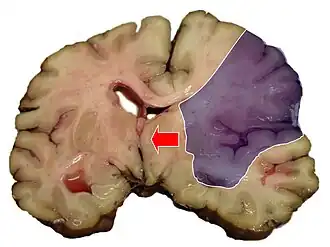

Hersenbloedingen

Hersenbloedingen ontstaan als een bloedvat in de hersenen openbarst. Als dit gebeurt krijgen de hersencellen die normaal door dit bloedvat van bloed worden voorzien geen voedingsstoffen en zuurstof meer en sterven af. Het bloed dat uit het bloedvat vloeit duwt het normale hersenweefsel weg. Door de samendrukking van hersenweefsel dat hierdoor kan optreden treedt verdere beschadiging op. Belangrijke oorzaken van hersenbloedingen zijn hoge bloeddruk, afwijkingen van de bloedvaten zoals aneurysmata en AVM's en hersentumoren.

CVA's kunnen worden ingedeeld in twee categorieën: herseninfarct en hersenbloeding.[6] Een herseninfarct ontstaat als de bloedtoevoer naar de hersenen wordt onderbroken. Een hersenbloeding kan ontstaan doordat een bloedvat scheurt of door een misvorming. Zo'n 87 procent van de beroertes zijn herseninfarcten en de rest zijn hersenbloedingen. Bij een herseninfarct kunnen er in het aangedane gebied bloedingen ontstaan. Dit wordt "hemorragische transformatie" genoemd. Het is niet bekend hoeveel hersenbloedingen beginnen als herseninfarct.[2]